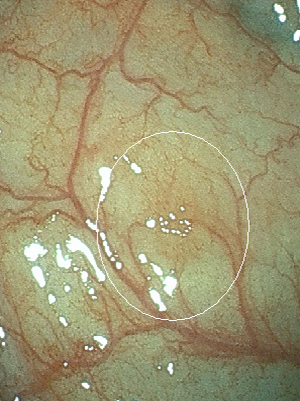

内視鏡検査の所見例

通常光(白色光)

通常光では淡い発赤ですが

特殊光-1

同じところを空気量調整し特殊光LCIにて観察

特殊-2

同じところを特殊光BLIにて血管と表面構造を観察

内視鏡検査の所見例

特殊光で炎症を強調して観察